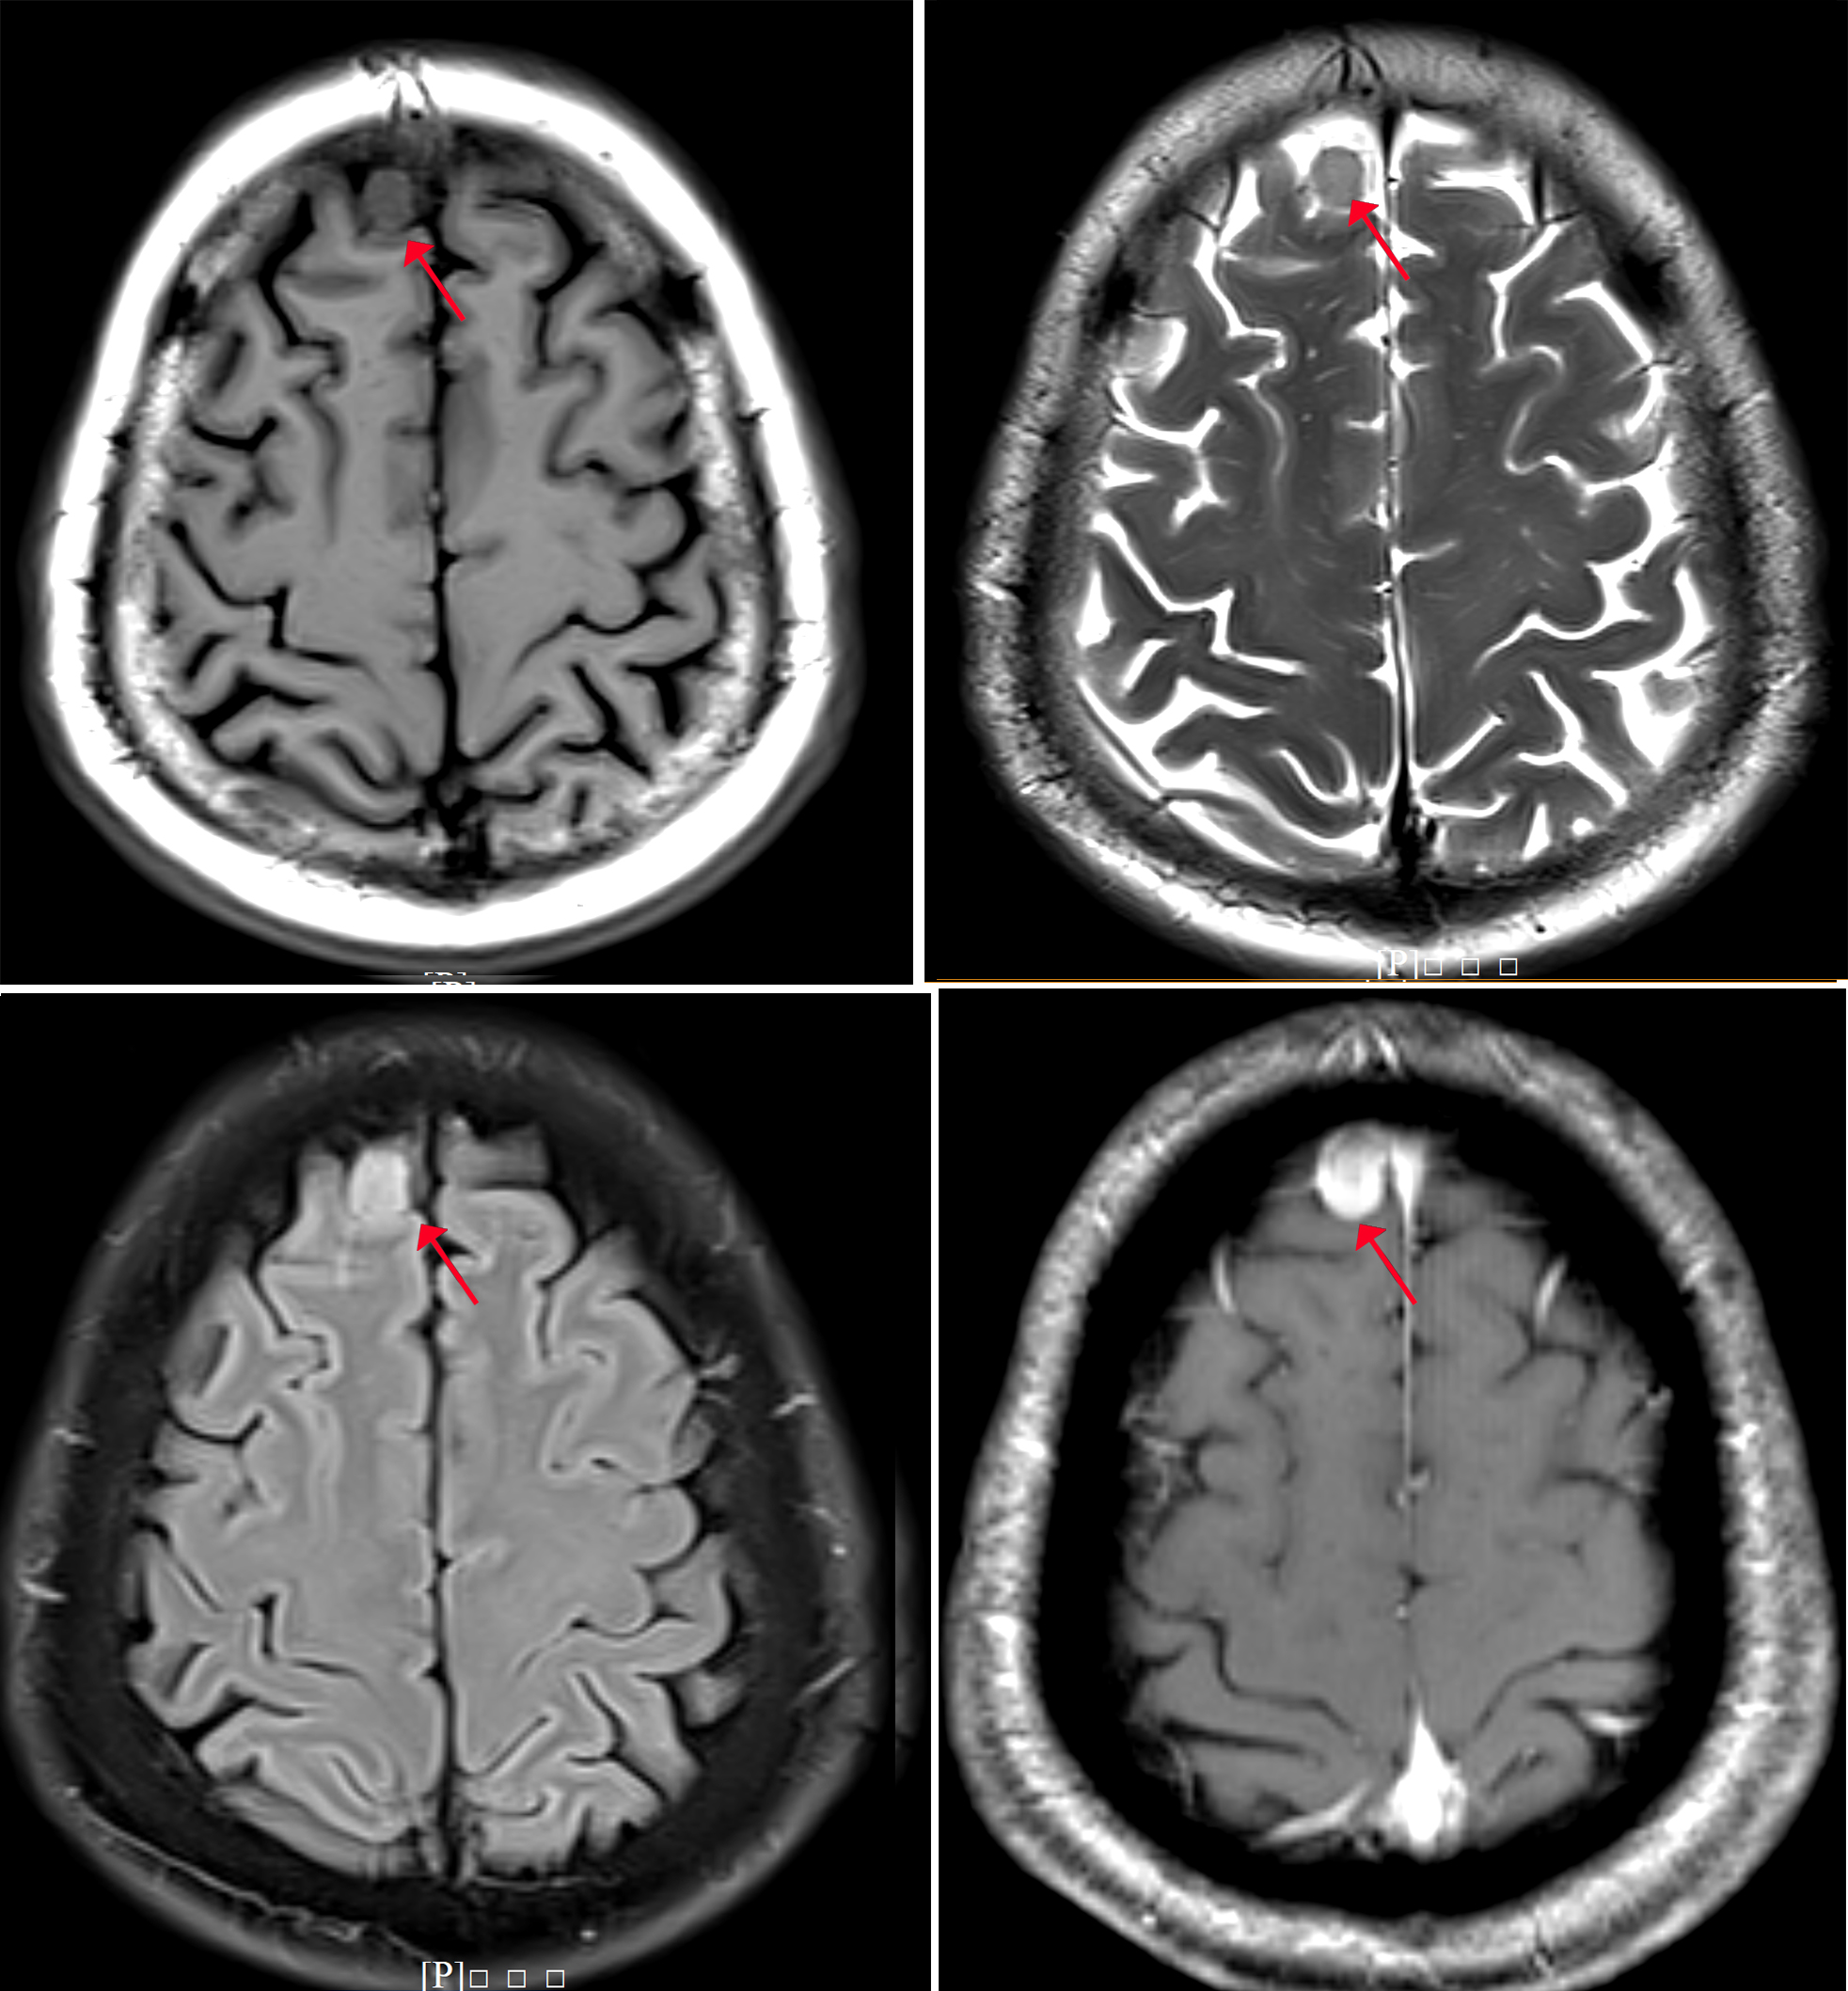

增強磁共振圖像

圖像所見:

顱腦磁共振增強掃描,于腦內右側額部見一枚類圓形明顯均勻強化占位性病變,大小約0.85X1.18X1.42cm,邊界清楚,信號均勻,病灶呈寬基底,于顱骨內板相連,臨近腦回受壓推移,周圍腦溝增寬,可見腦膜尾征。雙側側腦室旁,余腦實質內未見明顯異常。

印象:右側額葉占位性病變,考慮腦膜瘤。